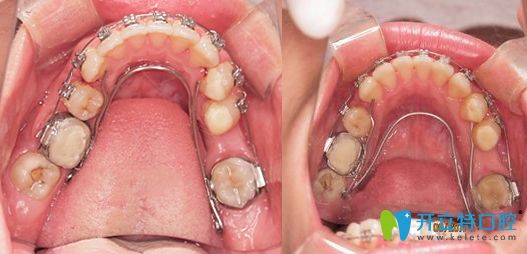

牙齒矯正擴(kuò)牙弓和拔牙對(duì)比圖